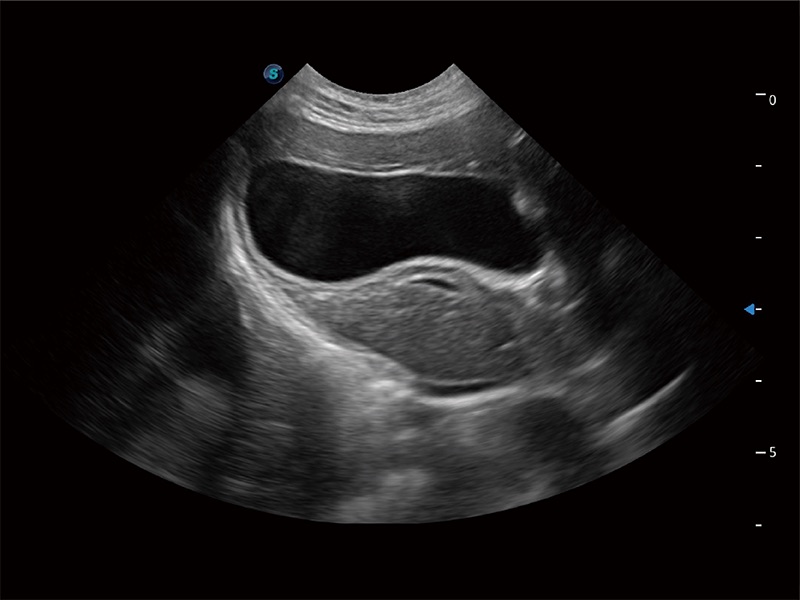

• Auto Bladder 膀胱自动测量

一键自动识别膀胱壁及自动测量膀胱容积,不受膀胱形状和大小的限制,帮助医生快速精准获得测量的数据。

(猫)胆囊